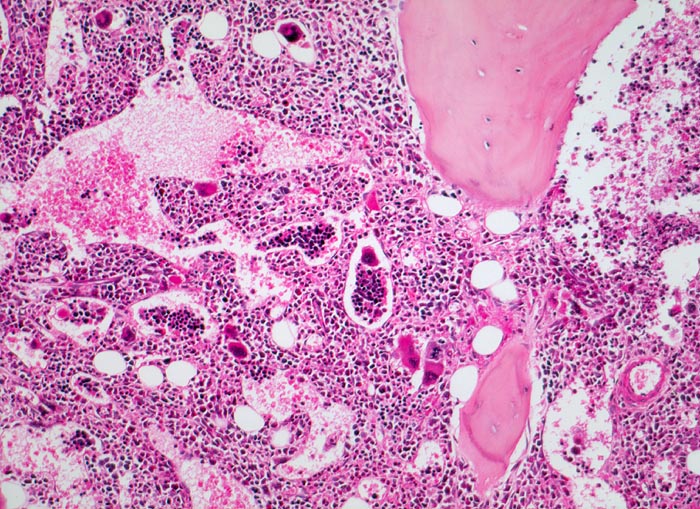

Die Erkrankung ist charakterisiert durch Knochenmarkfibrose, Hepato-Splenomegalie und extramedulläre Blutbildung. Diese findet sich am häufigsten in Leber und Milz, seltener in Lymphknoten, Nieren, Nebennieren, Dura mater, Gastrointestinaltrakt, Lunge, Mamma oder Haut. Blut und Knochenmark sind immer involviert. Die Krankheit entwickelt sich über ein initiales präfibrotisches Stadium mit hyperzellulärem Knochenmark zum fibrotischem Stadium (vorliegendes Präparat). Das fibrotische Stadium ist gekennzeichnet durch eine Vermehrung von Reticulin- und/oder Kollagenfasern und oft einer Knochenneubildung (=Osteomyelosklerose). Die Zellularität des Knochenmarks ist dann vermindert und dilatierte Marksinus enthalten intraluminale Blutbildungsherde. Es besteht eine auffallende Proliferation von Gruppen bildenden atypischen Megakaryozyten.

• Osteosklerose: verplumpte und breite Knochenbälkchen.

• Kollagenfibrose.

• Dilatierte Sinusoide mit intrasinusoidaler Blutbildung.

• Vermehrung von atypischen, in Gruppen liegenden Megakaryozyten mit abnorm lobulierten Kernen.

• Nacktkernige (zytoplasmaarme) und vergrösserte Megakaryozyten.

• Hyperplastische ausreifende Myelopoese.

• Hypoplastische Erythropoese.

• Retikulinfaserfibrose des Marks vorhanden aber in der HE Färbung schwierig quantifizierbar.